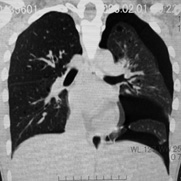

LAM患者さんに認められた両側肺気腫(右図:胸部CT)

secondCT.jpg

初診時CT(左)から2年後のCTでは肺の嚢胞化が著明となっている。